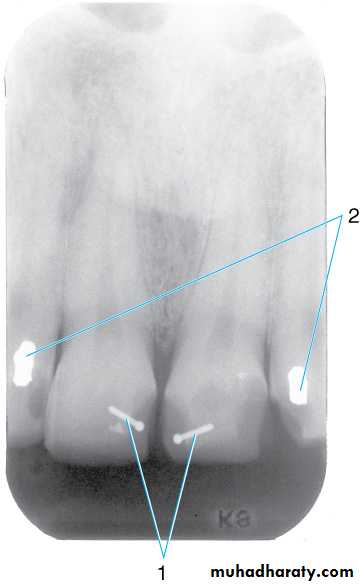

Retention pins. (1) Radiopaque pins help retain the radiolucent composite restorations. (2) Small radiopaque amalgam restorations.